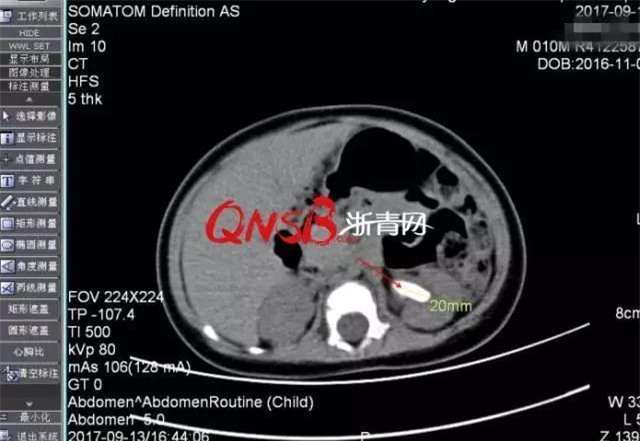

Kết quả chụp CT sỏi thận của Tiểu Ái.

Đến cả các bác sĩ cũng vô cùng ngạc nhiên khi phát hiện ra trong thận trái của bé trai 10 tháng tuổi có một viên sỏi đường kính 2cm và đường niệu quản bị giãn. Bác sĩ cho biết, nguyên nhân khiến bé bị sốt là do nhiễm trùng đường tiểu, sỏi cũng được kết thành từ đó. Đến tháng 9/2017, Tiểu Ái được chuyển đến bệnh viện Nhân dân tỉnh Chiết Giang để điều trị vì viên sỏi có kích cỡ vô cùng lớn đối với bệnh nhân ở độ tuổi này, nếu không điều trị kịp thời, chức năng thận của bé sẽ bị ảnh hưởng.